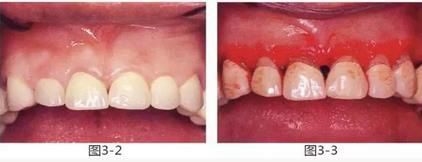

圖3-2 ,3

雖然存在較為淺度的牙周袋和齦下齲壞,但是從齦緣到牙槽嵴頂位置有充足的健全牙體組織和角化齦,因此通過牙齦切除進(jìn)行了治療。